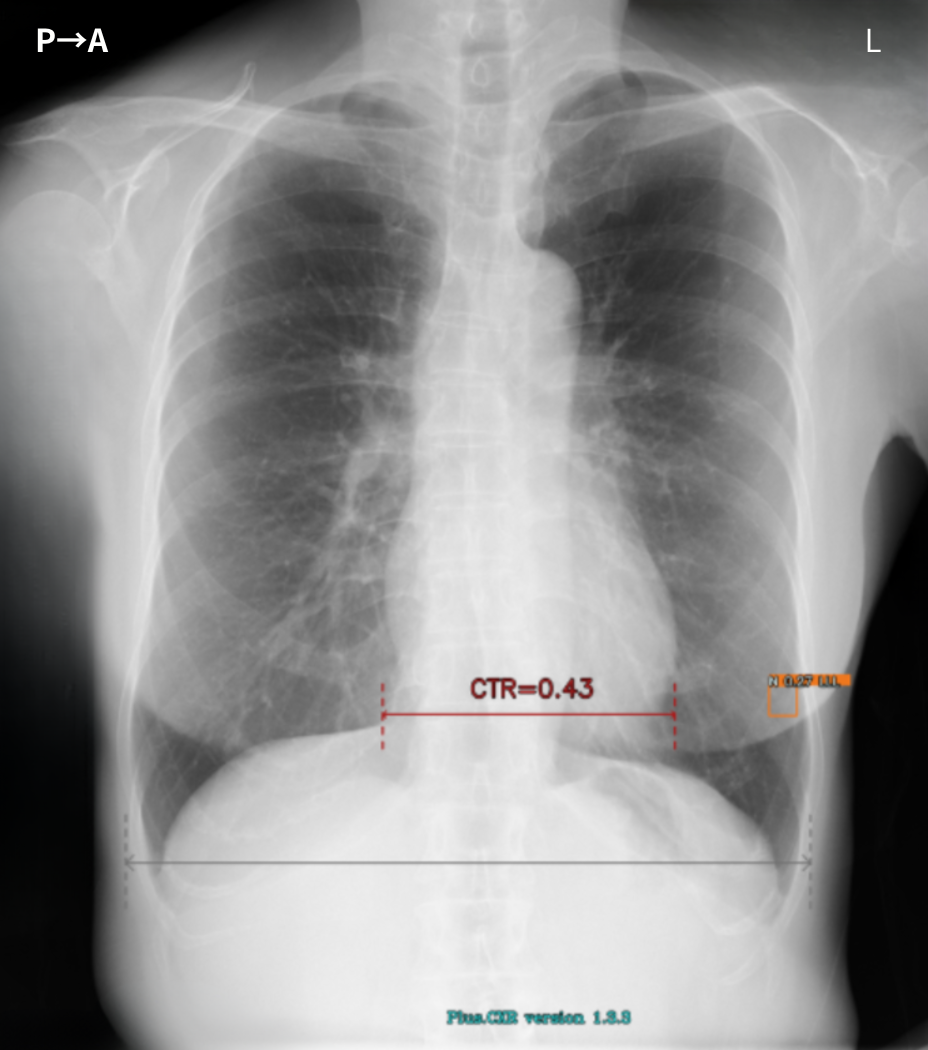

ここで胸部X線検査読影の手順を紹介します。内科診察室(あるいは2次読影室では)画像診断専用のモニターが2機準備されており、健診当日の胸部X線結果と直近の胸部X線画像が同時に供覧され、直ちに比較読影が行われます。さらに当日の胸部X線画面をスクロールすると、当初モニターで観察された2画像の経時的差分画像(サブトラクション画像)が表示されます。

さらにスクロールすることで、胸部X線AI「Plus.CXR」画像が表示されます。手元のマウスのコントローラーで容易に画像を切り替えられる仕様となっております。原則として、検査同日に2次読影判定を終了しております。

胸部X線AI「Plus.CXR」が指摘する、正常な乳頭陰影や肋骨肋軟骨移行部周囲の軟骨の骨化(Ossification)、各所の胸膜肥厚所見などの精査不要の陰性所見をより短時間でルールアウトできるようになりました。

また、胸部X線AI「Plus.CXR」では著者が通常は指摘できない、径5mm前後の比較的小さな病変を指摘できます。

加えて、肺門部周囲の太い血管陰影とシルエットが明瞭に存在する淡い透過性の低下部を指摘することができました。これらは、十分な集中力で画像を参照していない場合見落とす可能性が高い所見だと思料されます(図1,2,3)。